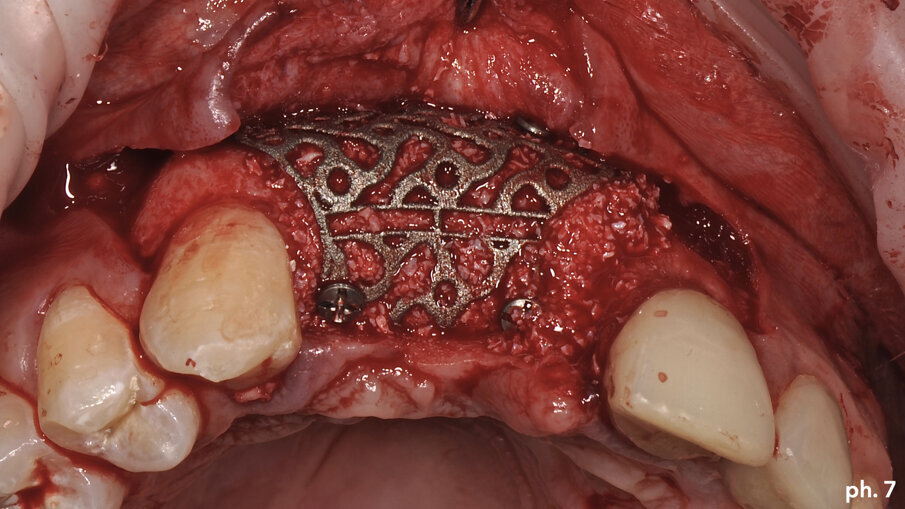

Una volta riempita la griglia con il mix di osso eterologo e autologo, la stessa è stata posizionata a livello del difetto e stabilizzata tramite l’utilizzo di viti di fissazione autofilettanti (Figg. 6, 7). Il grado di stabilità di queste griglie in titanio customizzate CAD/CAM è assolutamente elevatissimo, così come il loro grado di precisione. Stabilizzata in maniera perfetta la griglia, la stessa è stata ricoperta con uno strato di Geistlich Mucograft in modo da permettere la miglior maturazione possibile dei tessuti molli in fase di guarigione (Fig. 8). Al momento della chiusura del lembo è stato necessario effettuare un’incisione per il rilascio del periostio per ottenere una guarigione per prima intenzione, aspetto fondamentale affinché la maturazione di tali presìdi risulti perfetta. Il tempo di guarigione suggerito dalla letteratura prima della rimozione della griglia è di circa otto mesi; personalmente aspetto sempre 12 mesi prima di inserire impianti in una zona di osso rigenerato, e così è stato anche in questa situazione. L’immagine numero 9 rappresenta la guarigione a un anno di distanza e la relativa radiografia di controllo (Fig. 9). L’attesa così prolungata porta a far sì che la fase chirurgica della rimozione delle griglie in titanio sia l’aspetto più complesso di tutto il trattamento. Questo perché le aderenze di tipo fibroso che si creano tra i tessuti molli e la griglia stessa rendono difficile l’asportazione soprattutto a livello palatale e linguale (Fig. 10).